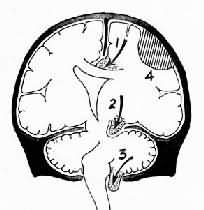

3.小脑扁桃体疝又称枕骨大孔疝。主要由于颅内高压或后颅凹占位性病变将小脑和延髓推向枕骨大孔并向下移位而形成小脑扁桃体疝。疝入枕骨大孔的小脑扁桃体和延髓成圆锥形,其腹侧出现枕骨大孔压迹(图16-8),由于延髓受压,生命中枢及网状结构受损,严重时可引起呼吸变慢甚至骤停,接着心脏停搏而猝死。

小脑扁桃体疝

图16-8 小脑扁桃体疝

示小脑切迹,两侧扁桃体疝形成